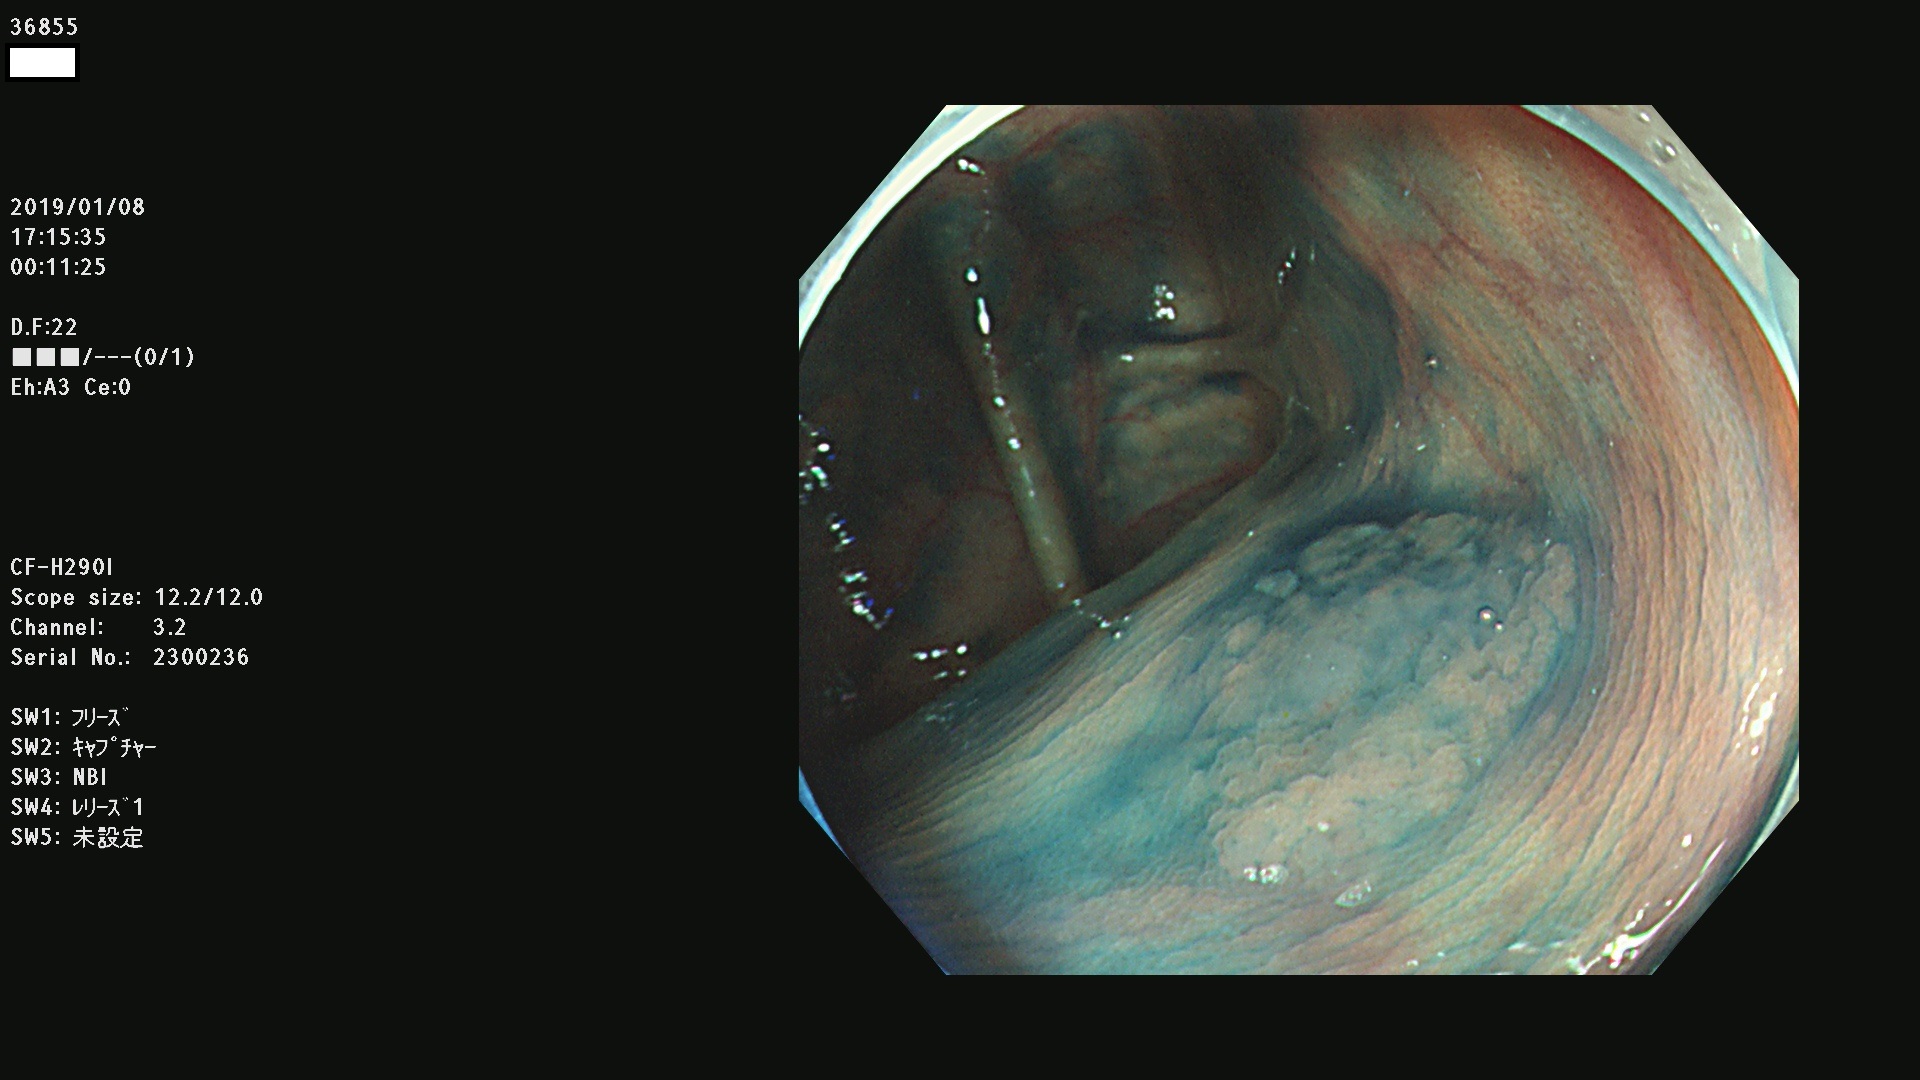

発見困難で危険性の高い平坦型病変(上記100名より抽出)

36804 36806 36807 36808 36809 36810 36811 36813 36815 36816 36817 36818 36820 36821 36822 36824 36825 36826 36828 36829 36830 36831 36832 36833 36834 36835 36837 36840 36841 36842 36845 36846 36848 36849 36851 36852 36853 36854 36855 36857 36859 36860 36861 36862(SSAPのみ) 36863 36864 36866 36868 36869 36870 36873 36875 36877 36878 36879 36881 36882 36883 36884 36885 36886 36887 36888 36889 36891 36892 36893 36894 36895 36896 36897 36898 36899